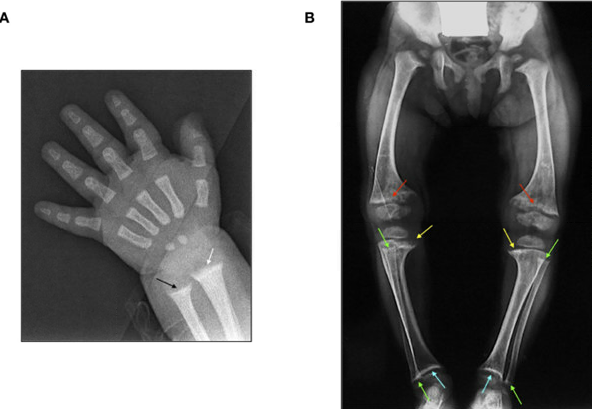

When children don’t get enough vitamin D, their bones may not form properly, leading to weaker bone structure. One serious condition, nutritional rickets, occurs when bones fail to mineralize correctly, causing deformities and a higher risk of fractures.

Studies show that children with low vitamin D levels are more than twice as likely to experience fractures compared to those with normal levels. The good news is that vitamin D deficiency—and the bone problems it causes—are completely preventable with proper nutrition and care.